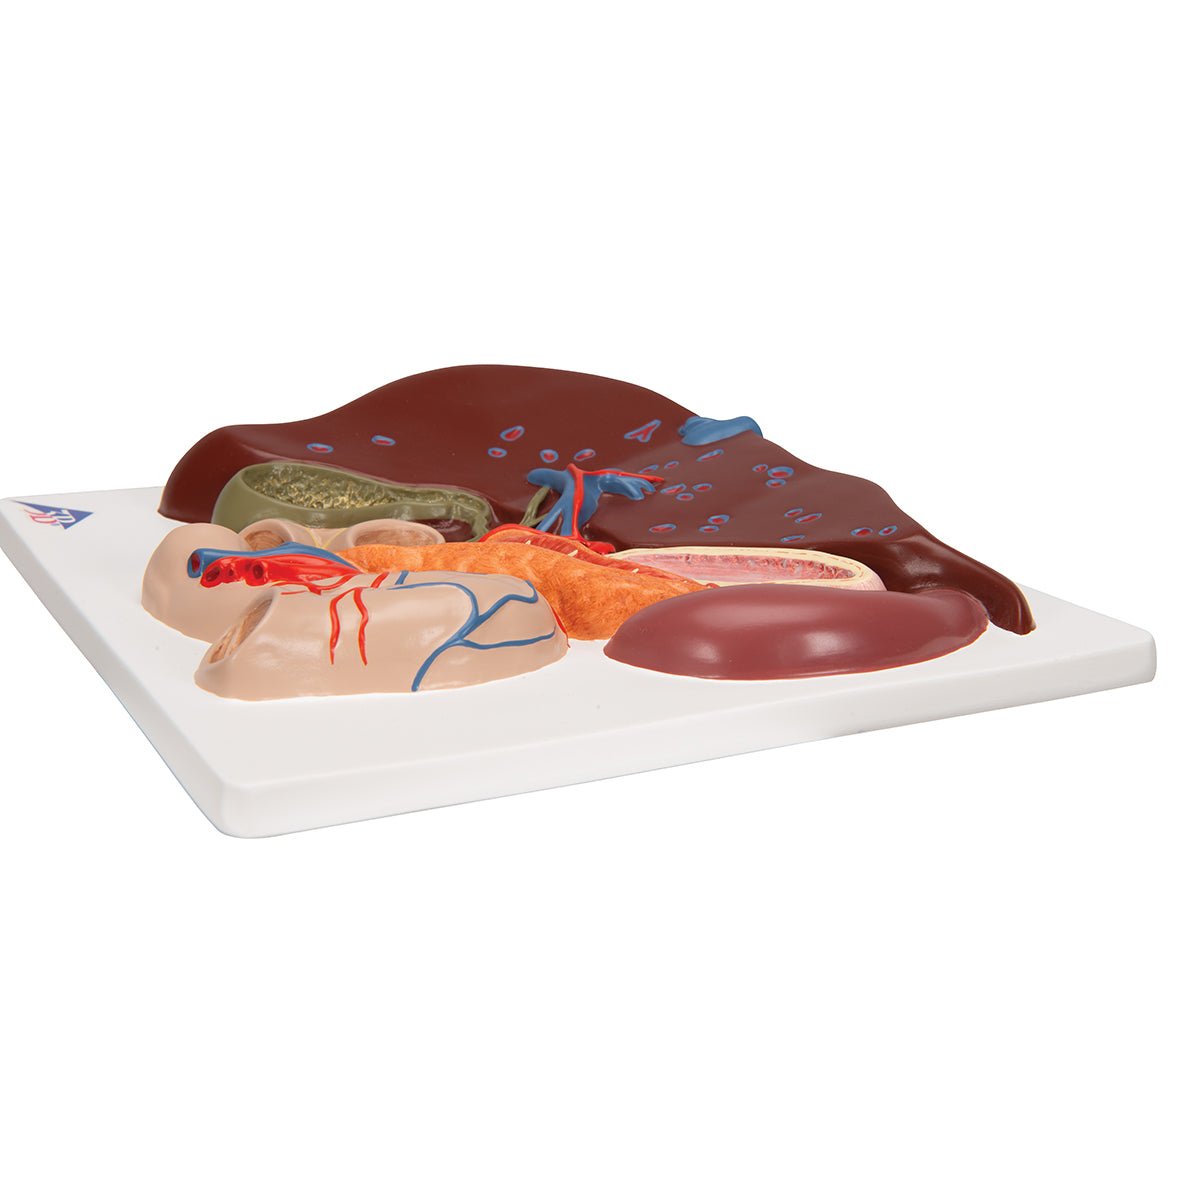

Salg af anatomiske modeller er det bærende element i eAnatomi, selvom vi også bruger mange ressourcer på at udvikle vores egne anatomiske materialer som fx plakater. Anatomiske modeller anvendes til forskellige formål og kan både vise afgrænset væv, organer samt organsystemer. Søger du en simpel model af knoglevæv eller måske en avanceret torso-model baseret på MRI teknologi, kan du finde det hele på eanatomi.com.